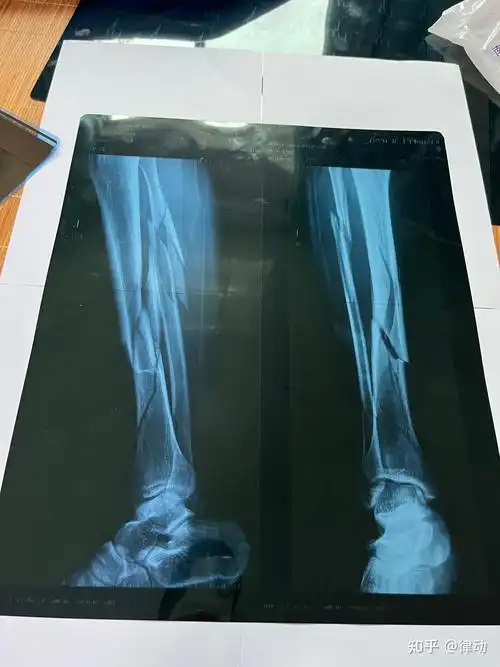

腓骨骨折过程 - 知乎

左小腿胫腓骨粉碎性骨折整个历程记录 - 知乎